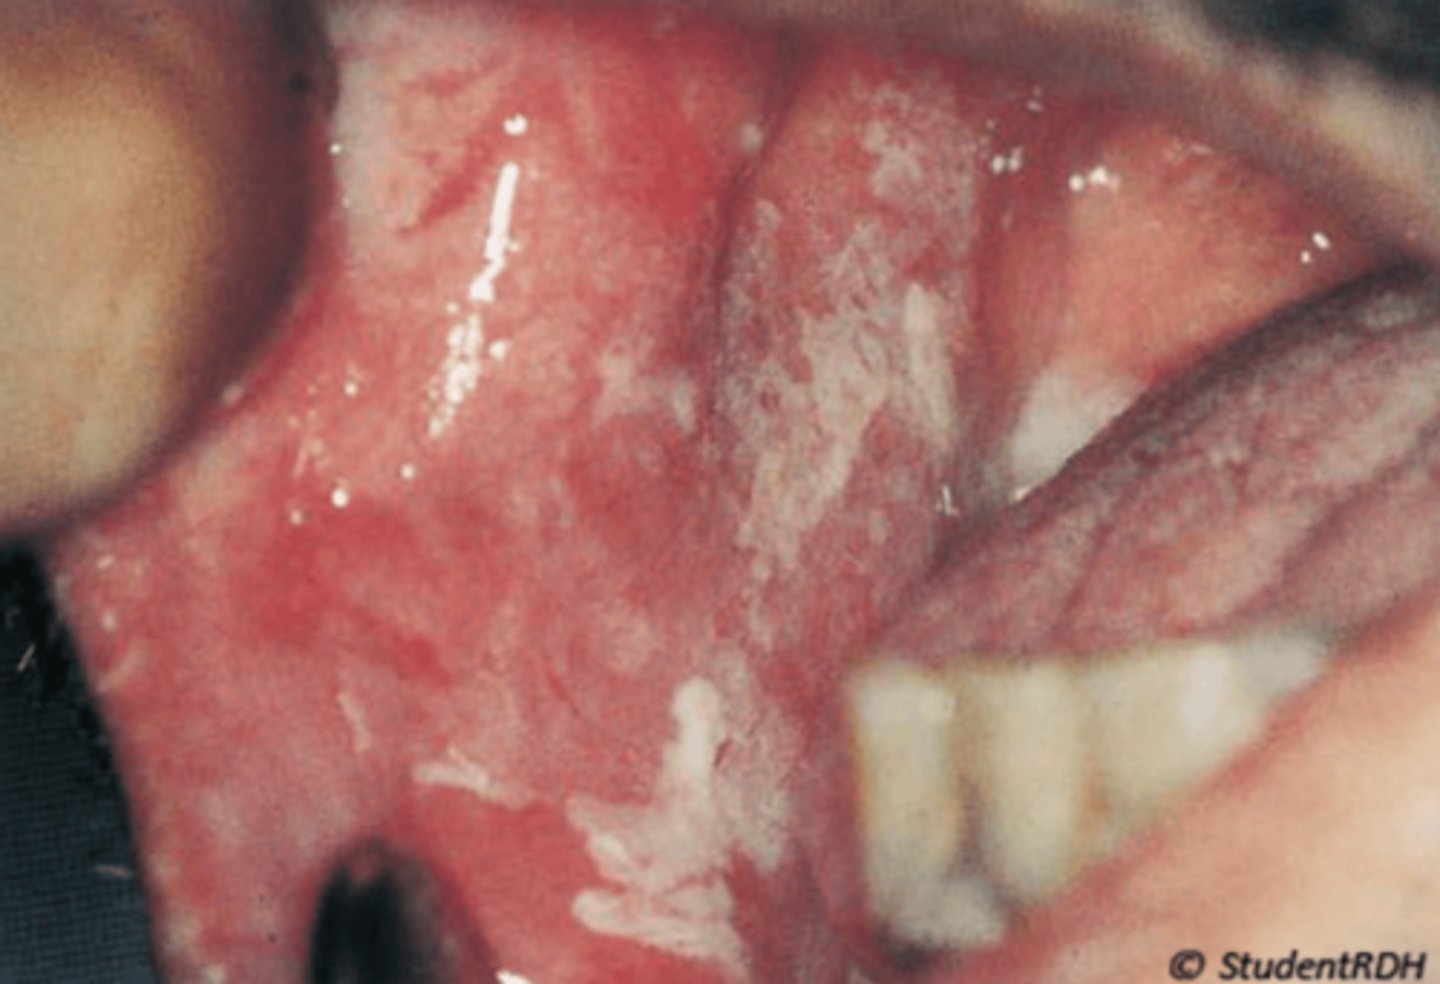

What is pseudomembranous candidiasis?

cheesy white plaques that wipe off

⢠leaves red, tender surface

⢠no bleeding